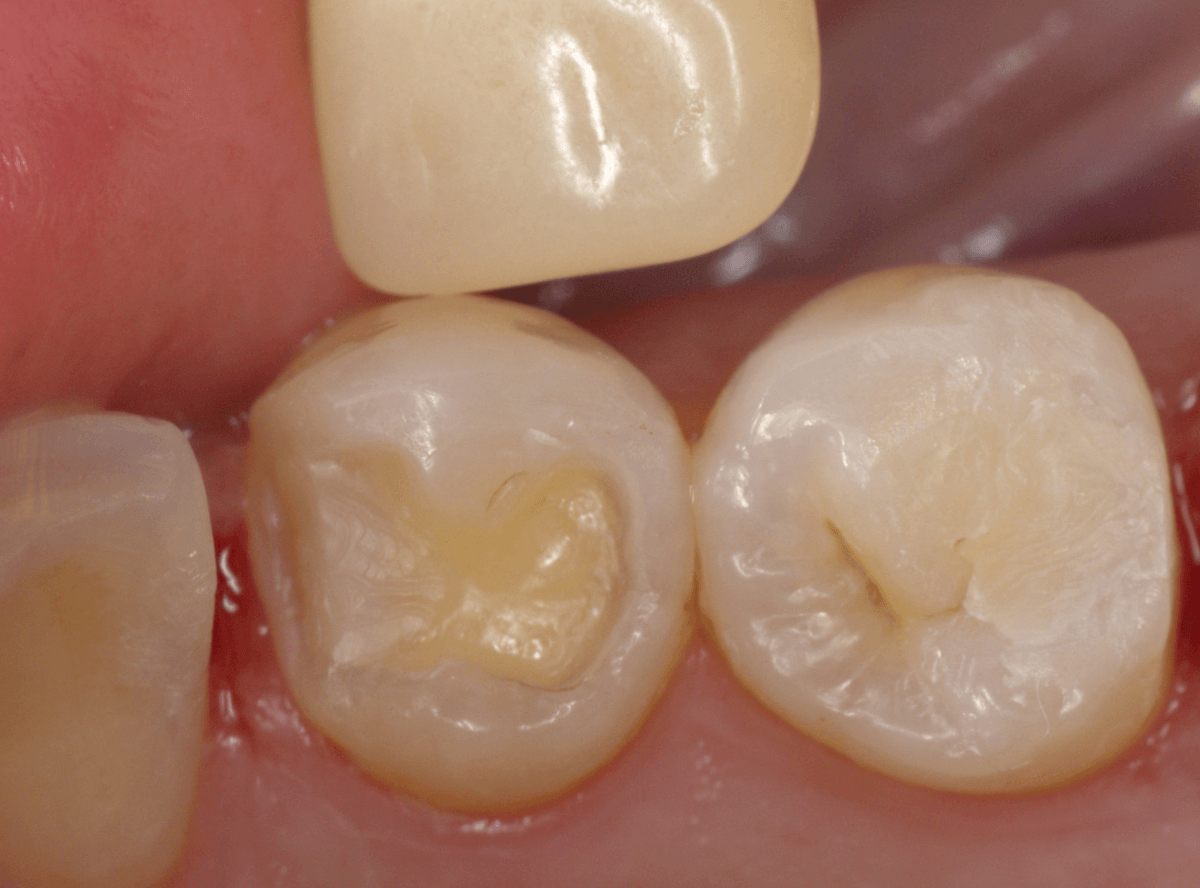

Case.28 虫歯治療後、半年以上来院されなかった患者さん

虫歯を治療して、セメントで歯を削った部分を封鎖した後、再修復を検討中で、半年以上来院されなかった患者さんです。

虫歯を治療して、セメントで封鎖した状態というのは、家でいえば、しっかりした屋根がない状態です。

今回は、セメントの一部がはがれる程度で済んでいましたが、虫歯が再発し、再治療、最終修復物の変更の可能性も出てきます。

皆さんも治療は中断せずに最後まで通院するようにしてくださいね。

治療再開後、セラミックの最終修復を希望されましたので、歯をトリミングし、型取りします。

模型上で精密に製作します。

治療後の状態です。

治療後の定期メンテナンスに来院されない患者さんもまれにいらっしゃいますが、一定期間来院のない方は破折などの際の保証も受けられません。

くれぐれも忘れずに来院していただくようにお話しし、終了となりました。